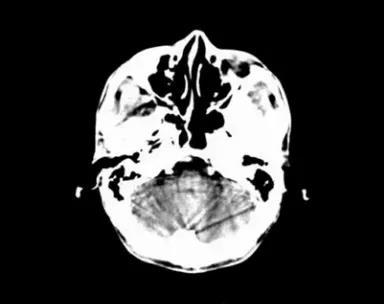

部分容积效应产生的伪影:

- 部分容积效应伪影的形状可能因为物体的不同而不一样,一般在重建后横断面图像上可见条形、环形或大片干扰的伪像。最常见和典型的现象是在头颅横断面时的颞部出现的条状伪影,又称哼氏伪影。

- 可采用薄层扫描而减弱,比如在西门子系列的CT机中,用VAR扫描技术可抑制该伪影。